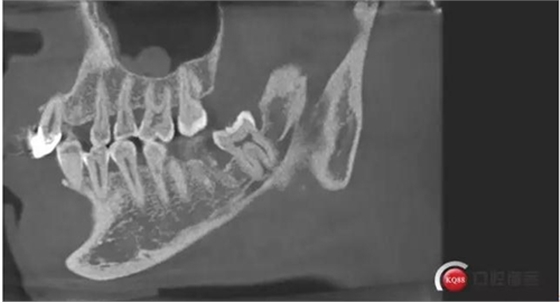

下面拔除后的片子,可以清楚的看到,牙根穿破神經(jīng)管。

拔牙前后對(duì)比一下,(拔除前)

1500633362_825152.jpg拔除后。 可以看到神經(jīng)管皮質(zhì)骨的不連續(xù)。